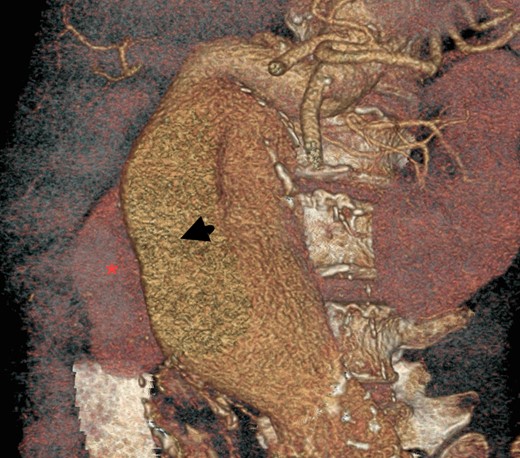

Decision of open repair of AAA was made. After stopping warfarin and reversing its effect, insertion of IVC filter was performed before the surgery. The inferior venogram during this procedure showed that the IVC was displaced to the right with external compression secondary to this large aortic aneurysm (Fig. 5).

A diagnosis of large AAA causing PE was made as it was found to be displacing and compressing the IVC, and causing venous thromboembolism. During the open repair of aortoiliac aneurysm, findings of venogram were confirmed, as aneurysm was found to be compressing IVC (Fig. 6). A large plaque was removed from the aneurysmal sac. A bifurcation synthetic graft was placed for inlay reconstruction, and the abdomen was closed in layers. Her recovery period was uneventful. She was able to sit on the chair on Day 3 after surgery and was mobilizing well in a week time.

Three-dimensional construction of CT aortogram showing displaced and compressed IVC (asterisk) due to large AAA (arrow head).